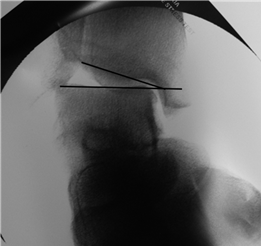

Weight-bearing anteroposterior (AP), lateral, and sesamoid axial radiographs are mandatory. On the AP view, the surgeon measures the Hallux Valgus Angle (HVA, normal < 15°), the Intermetatarsal Angle (IMA, normal < 9°), and the Distal Metatarsal Articular Angle (DMAA). The lateral view is scrutinized for Meary's angle (talo-first metatarsal angle) to identify midfoot collapse, as well as the presence of dorsal osteophytes indicative of hallux rigidus. The sesamoid axial view is critical for assessing the degree of sesamoid subluxation and the integrity of the crista.

Digital templating software is employed to determine the center of rotation of angulation (CORA) and to simulate the proposed osteotomy or fusion. This allows the surgeon to anticipate the degree of translation required, the potential for metatarsal shortening, and the appropriate size of fixation hardware. For a Lapidus procedure, templating helps calculate the exact wedge of bone to be resected from the medial cuneiform and first metatarsal base to achieve the desired multiplanar correction.

To achieve multiplanar correction, the surgeon must address the sagittal, coronal, and transverse planes. The first metatarsal is plantarflexed to restore the longitudinal arch, rotated out of pronation to realign the sesamoids, and translated laterally to close the IMA. Subchondral drilling or feathering is performed to optimize the biological environment for fusion. Fixation is traditionally achieved with two or three crossed solid or cannulated screws (typically 3.5mm or 4.0mm). Recently, plantar or medial locking plates have gained immense popularity due to their superior biomechanical construct, allowing for earlier weight-bearing. Bone graft or orthobiologics may be packed into the arthrodesis site to stimulate osteogenesis.